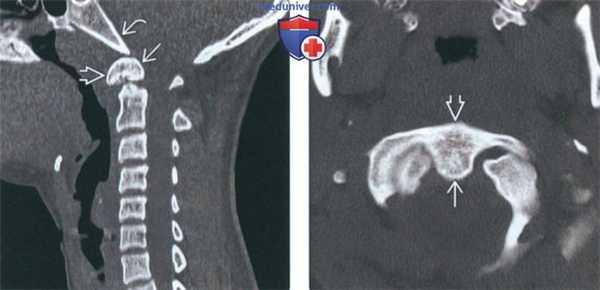

(Слева) На сагиттальной КТ шейного отдела позвоночника в костном окне определяется врожденное слияние передней дуги С1 и крупной зубовидной кости. Соотношение зубовидной кости со скатом не нарушено. Шейный отдел позвоночника ниже осевого позвонка в остальном не изменен, нарушения сегментации других позвонков не выявлены.

(Справа) На аксиальной КТ в костном окне определяется врожденное слияние орто-топической зубовидной кости с передней дугой С1 по средней линии. Задняя дуга С1 не имеет дефектов (на этом срезе не видна).

(Слева) На сагиттальной КТ в костном окне определяется слияние дистопической зубовидной кости с передней дугой С1. Вершина ската минимально ремоделирована (уплощена). Определяется дисплазия короткого и округлого зубовидного отростка.

(Справа) На корональной КТ в костном окне определяется эксцентрическое слияние дистопической зубовидной кости с передней дугой и боковой массой С1 слева. Обратите также внимание на патологический псевдосустав между зубовидной костью и левым затылочным мыщелком.

(Справа) Это сагиттальное Т2-ВИ получено в положении разгибания и отражает нормальное расположение зубовидной кости. В положении сгибания эта кость смещается кпереди, что свидетельствует об атлантоаксиальной нестабильности. (Слева) КТ шейного отдела позвоночника, сагиттальный срез: врожденное сращение передней дуги С1 и крупной зубовидной костив. Нормальные взаимоотношения между скатом В и зубовидной костью сохранены. Субаксиальные сегменты шейного отдела позвоночника во всех отношениях нормальны, признаков каких-либо других аномалий сегментации не выявлено.

(Справа) Аксиальный КТ-срез подтверждает наличие прочного врожденного сращения ортотопичной зубовидной кости с передней дугой С1. Задняя дуга С1 сформирована полностью (здесь не видно). (Слева) КТ, сагиттальный-срез: сращение крупной дистопичной зубовидной кости с передней дугой С1. Вершина ската с признаками минимального ремоделирования (уплощена). Укороченный и закругленный зубовидный отросток диспластичен.

(Справа) На фронтальном КТ-срезе представлен случай эксцентричного сращения дистопичной зубовидной кости с левой половиной передней дуги С1 и его боковой массой. Обратите также внимание на наличие аномального неоартроза между зубовидной костью и левым мыщелком затылочной кости.